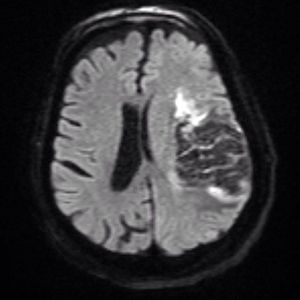

T2 blackout effect is a diffusion weighted imaging (DWI) phenomenon, representing the reverse of T2 shine through. In T2-blackout effect, lesions with very short T2 (and/or T2*) values reduce signal intensity in the DW image, potentially masking or destroying its diffusion sensitivity. In extreme cases even the ADC map calculation will be affected and unreliable. Image shared by @radiopaedia